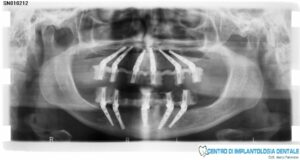

Nel nostro Centro di Implantologia Dentale abbiamo importato questa tecnica, ormai così consolidata che riporta consensi positivi a livello mondiale, personalizzandola con l’aggiunta di due impianti nell’arcata superiore (realizzando una arcata dentaria di 12 denti sostenuta da 6 impianti)

e un impianto nell’arcata inferiore (realizzando una arcata dentaria di 12 denti sostenuta da 5 impianti).

Nel nostro Centro abbiamo scelto di utilizzare un numero superiore di impianti rispetto alla tecnica di Malò in modo da assicurare nel tempo una maggiore affidabilità e durata degli impianti così sottoposti ad un carico masticatorio di 12 denti (come nostro protocollo testato). La personalizzazione della tecnica è stata eseguita a diversi livelli, che vanno dalla progettazione tecnologica dell’intervento, al controllo totale della sintomatologia intra e post operatoria, alla guida alimentare post chirurgica e alla educazione del paziente alle nuove tecniche di igiene orale.